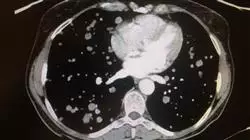

• Понять роль новых тестов, таких как позитронно-эмиссионная томография при раке шейки матки

• Оценить полезность ПЭТ-КТ для оценки метаболизма при поражениях, подозрительных на злокачественность